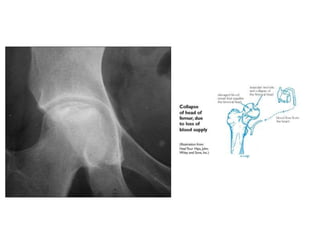

– Osteonecrosis (avascular necrosis)

• Can occur with & without history of steroid therapy